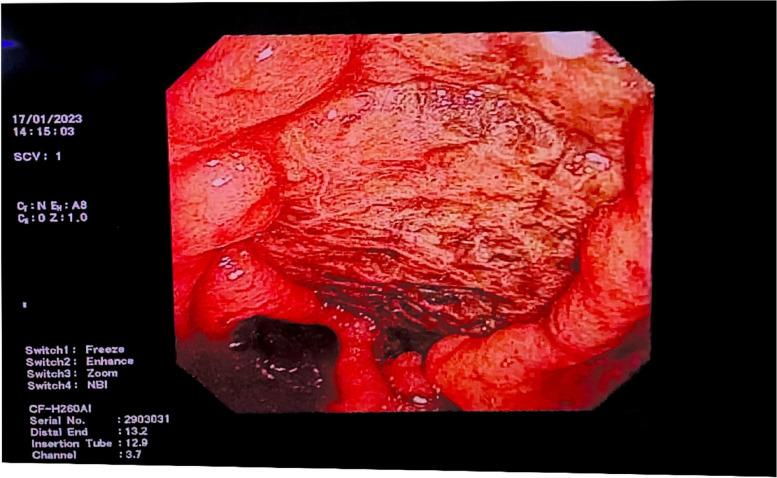

Herein, we report the case of an 81-year-old woman admitted to the emergency department due to severe COVID-19 and transferred to the ICU 2 days later for treatment. During treatment in the ICU, the patient developed recurrent duodenal ulcer bleeding and underwent endoscopic electrocoagulation haemostasis and gastroduodenal artery embolisation. However, the night after the final haemostatic operation, due to rectal ulcer bleeding, the patient discharged bloody stools intermittently, which was effectively controlled using endoscopic electrocoagulation, topical medication, blood transfusion, and haemostatic drugs.

在此,我们报告了一例 81 岁女性,因重症 COVID-19 入住急诊科,2 天后转入 ICU 治疗。在 ICU 治疗期间,患者发生反复十二指肠溃疡出血,并接受了内镜电凝止血和胃十二指肠动脉栓塞。然而,最后一次止血手术后的当晚,由于直肠溃疡出血,患者间歇性排出带血粪便,经内镜电凝、局部用药、输血和止血药物治疗后有效控制。